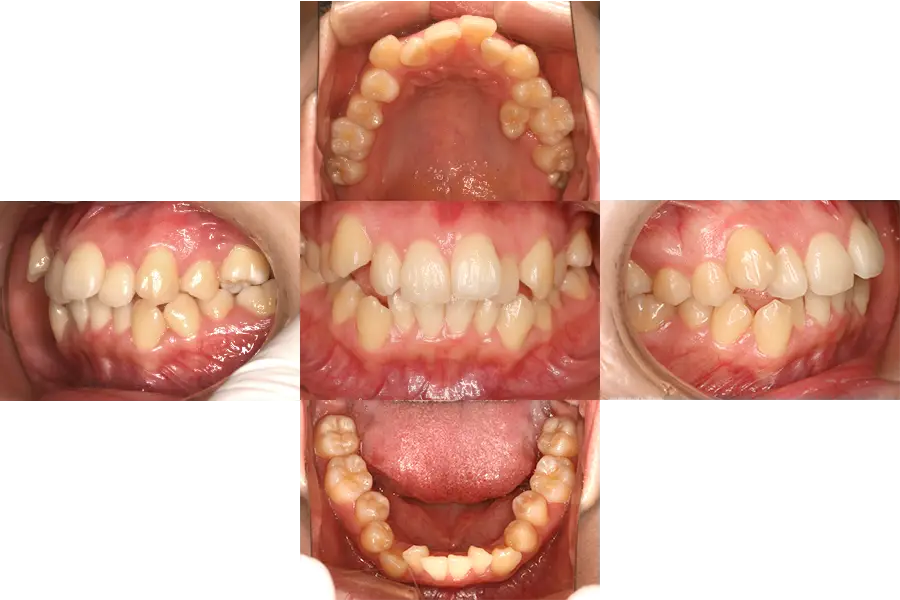

- 上下の前歯に重度の凸凹(ガチャ歯)があり歯が磨きにくく、また、上の前歯が出ていて、物が咬み切れず、さらに、上の前歯出ているため口が閉じられない。ずっと治したいと思っていたが、装置が目立つのが気になるので、他の人に気が付かれない方法で治したい

- 上下顎のあごの骨のずれがあり、さらに上下の前歯に重度の凸凹と著しい上の前歯が認められる。また、唇を閉じようとすると上の前歯がでて閉じられない